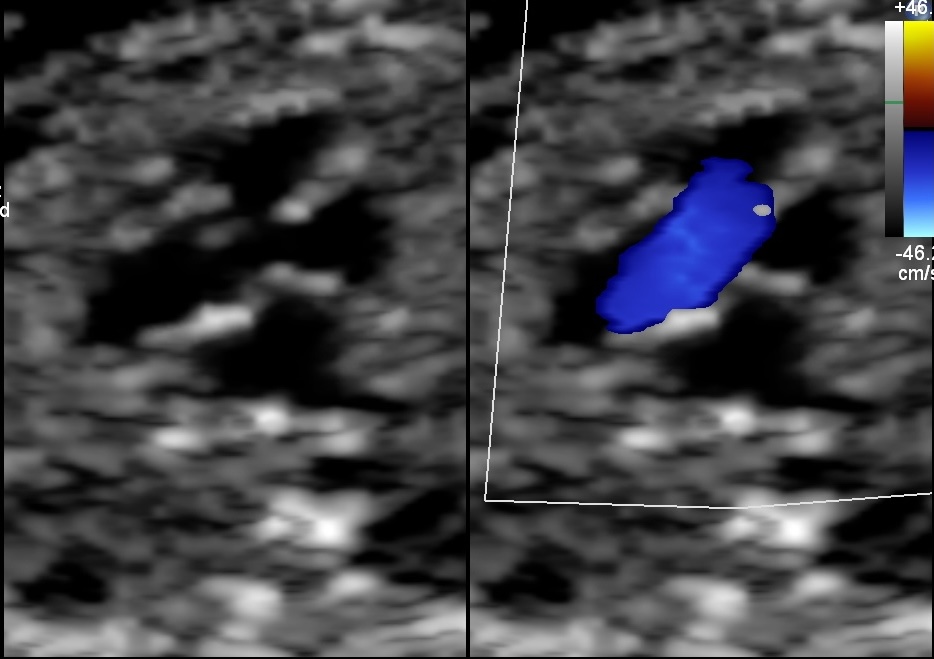

Image: Case of Fetal ToF with Right Aortic Arch with a significantly small pulmonary artery and a small Thymus. Dipicting high-risk features for the likelihood of the post-natal duct dependency and association with 22q11 deletion.